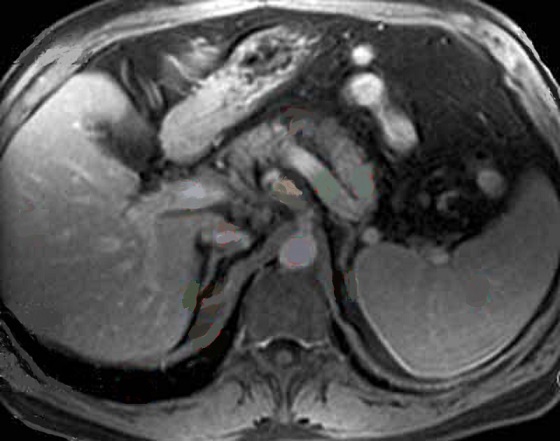

Aspect de la rate au temps de evacuation

apres injection de chelate de Gadolinium . Le

parenchyme de la rate est homogene et isosignal par

rapport au foie |

Dynamique de rehaussement de la rate apres

injection de Gadolinium intraveineuse |